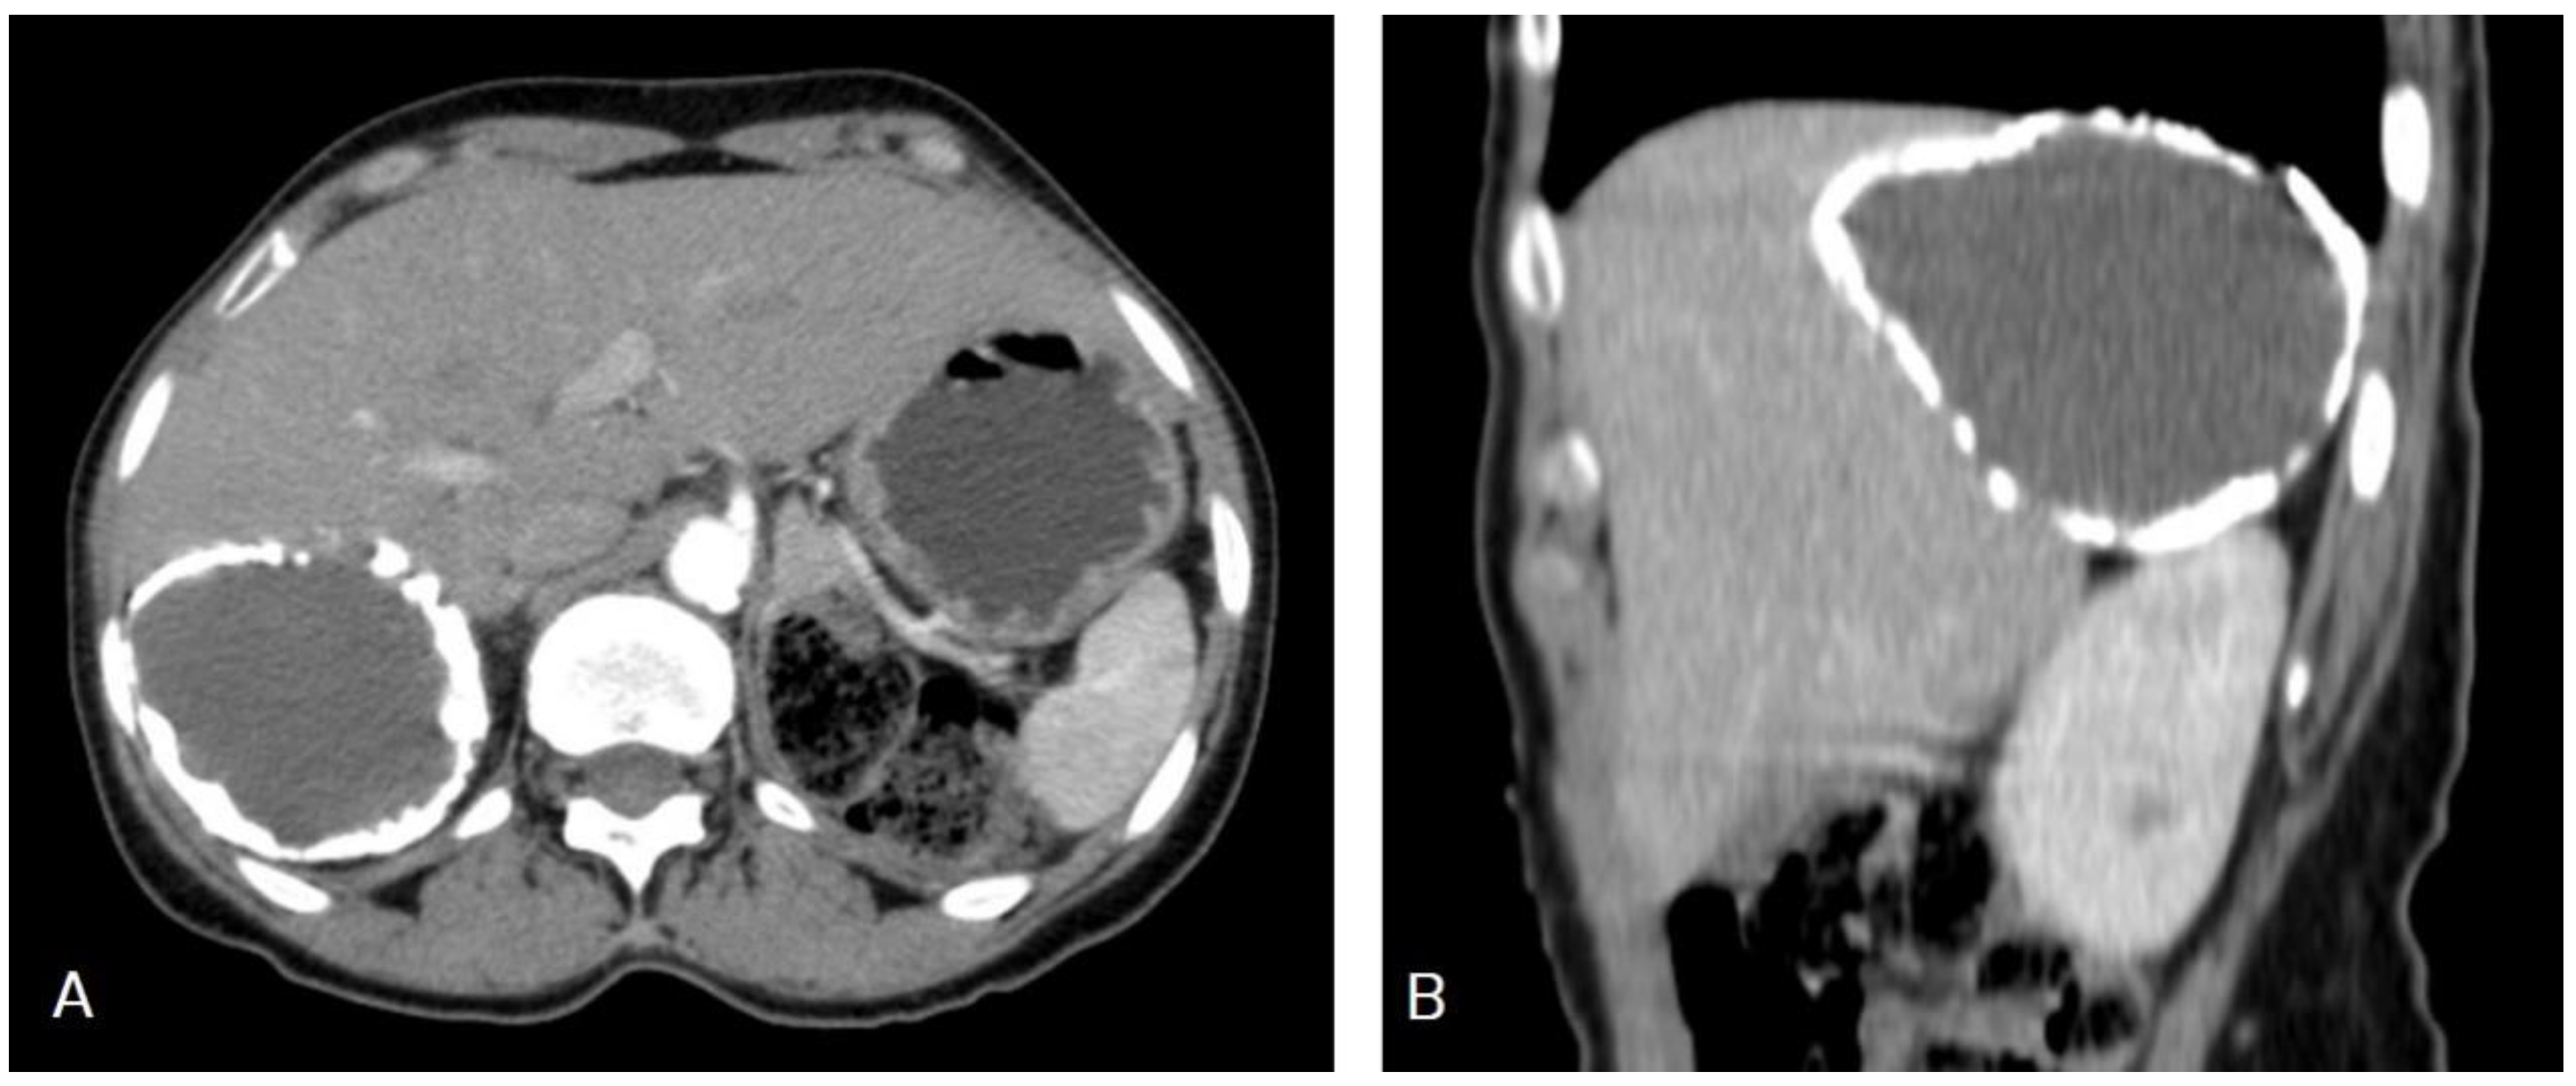

5.1. Hydatid Cysts of the Liver